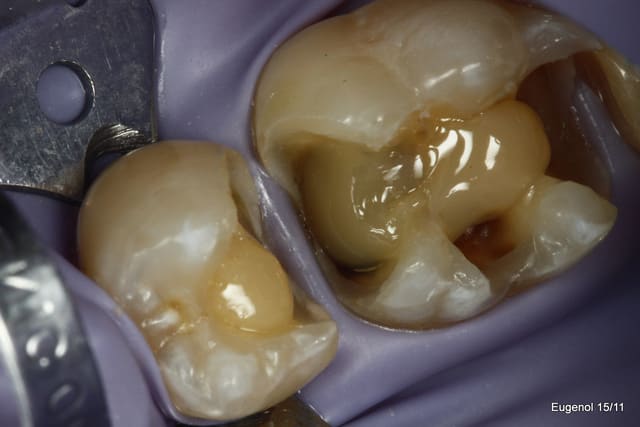

un truc que je fais souvent, quand je monte deux compo volumineux en contact, je monte le plus gros et difficile sans matrice et comme ça j'ai accès a la marge, et je peux donner une jolie forme galbée proximale

puis je monte le suivant avec une seule matrice...

plus facile je trouve d'avoir le point de contact

SC12 (35) SC17 (36) sc7 + sc7 (37), 50mn ...

maquillant Enamel HFO